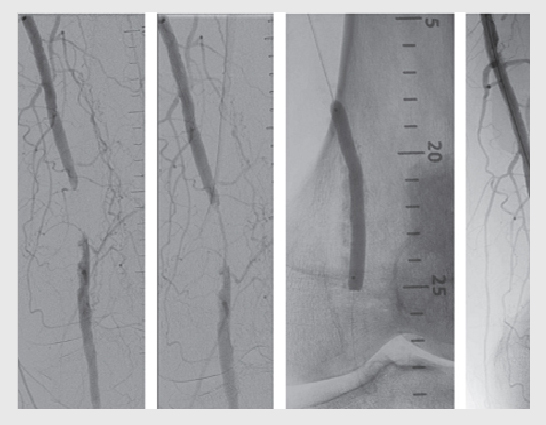

Peripheral coronary Interventions for blockage in the leg arteries

3. Angioplasty and stenting: In some cases, minimally invasive procedures like angioplasty (using a balloon to widen the artery) and stent placement (to keep the artery open) may be performed to improve blood flow.

4. Atherectomy: As mentioned earlier, atherectomy may be used to remove plaque from the arteries and improve blood flow in certain cases.